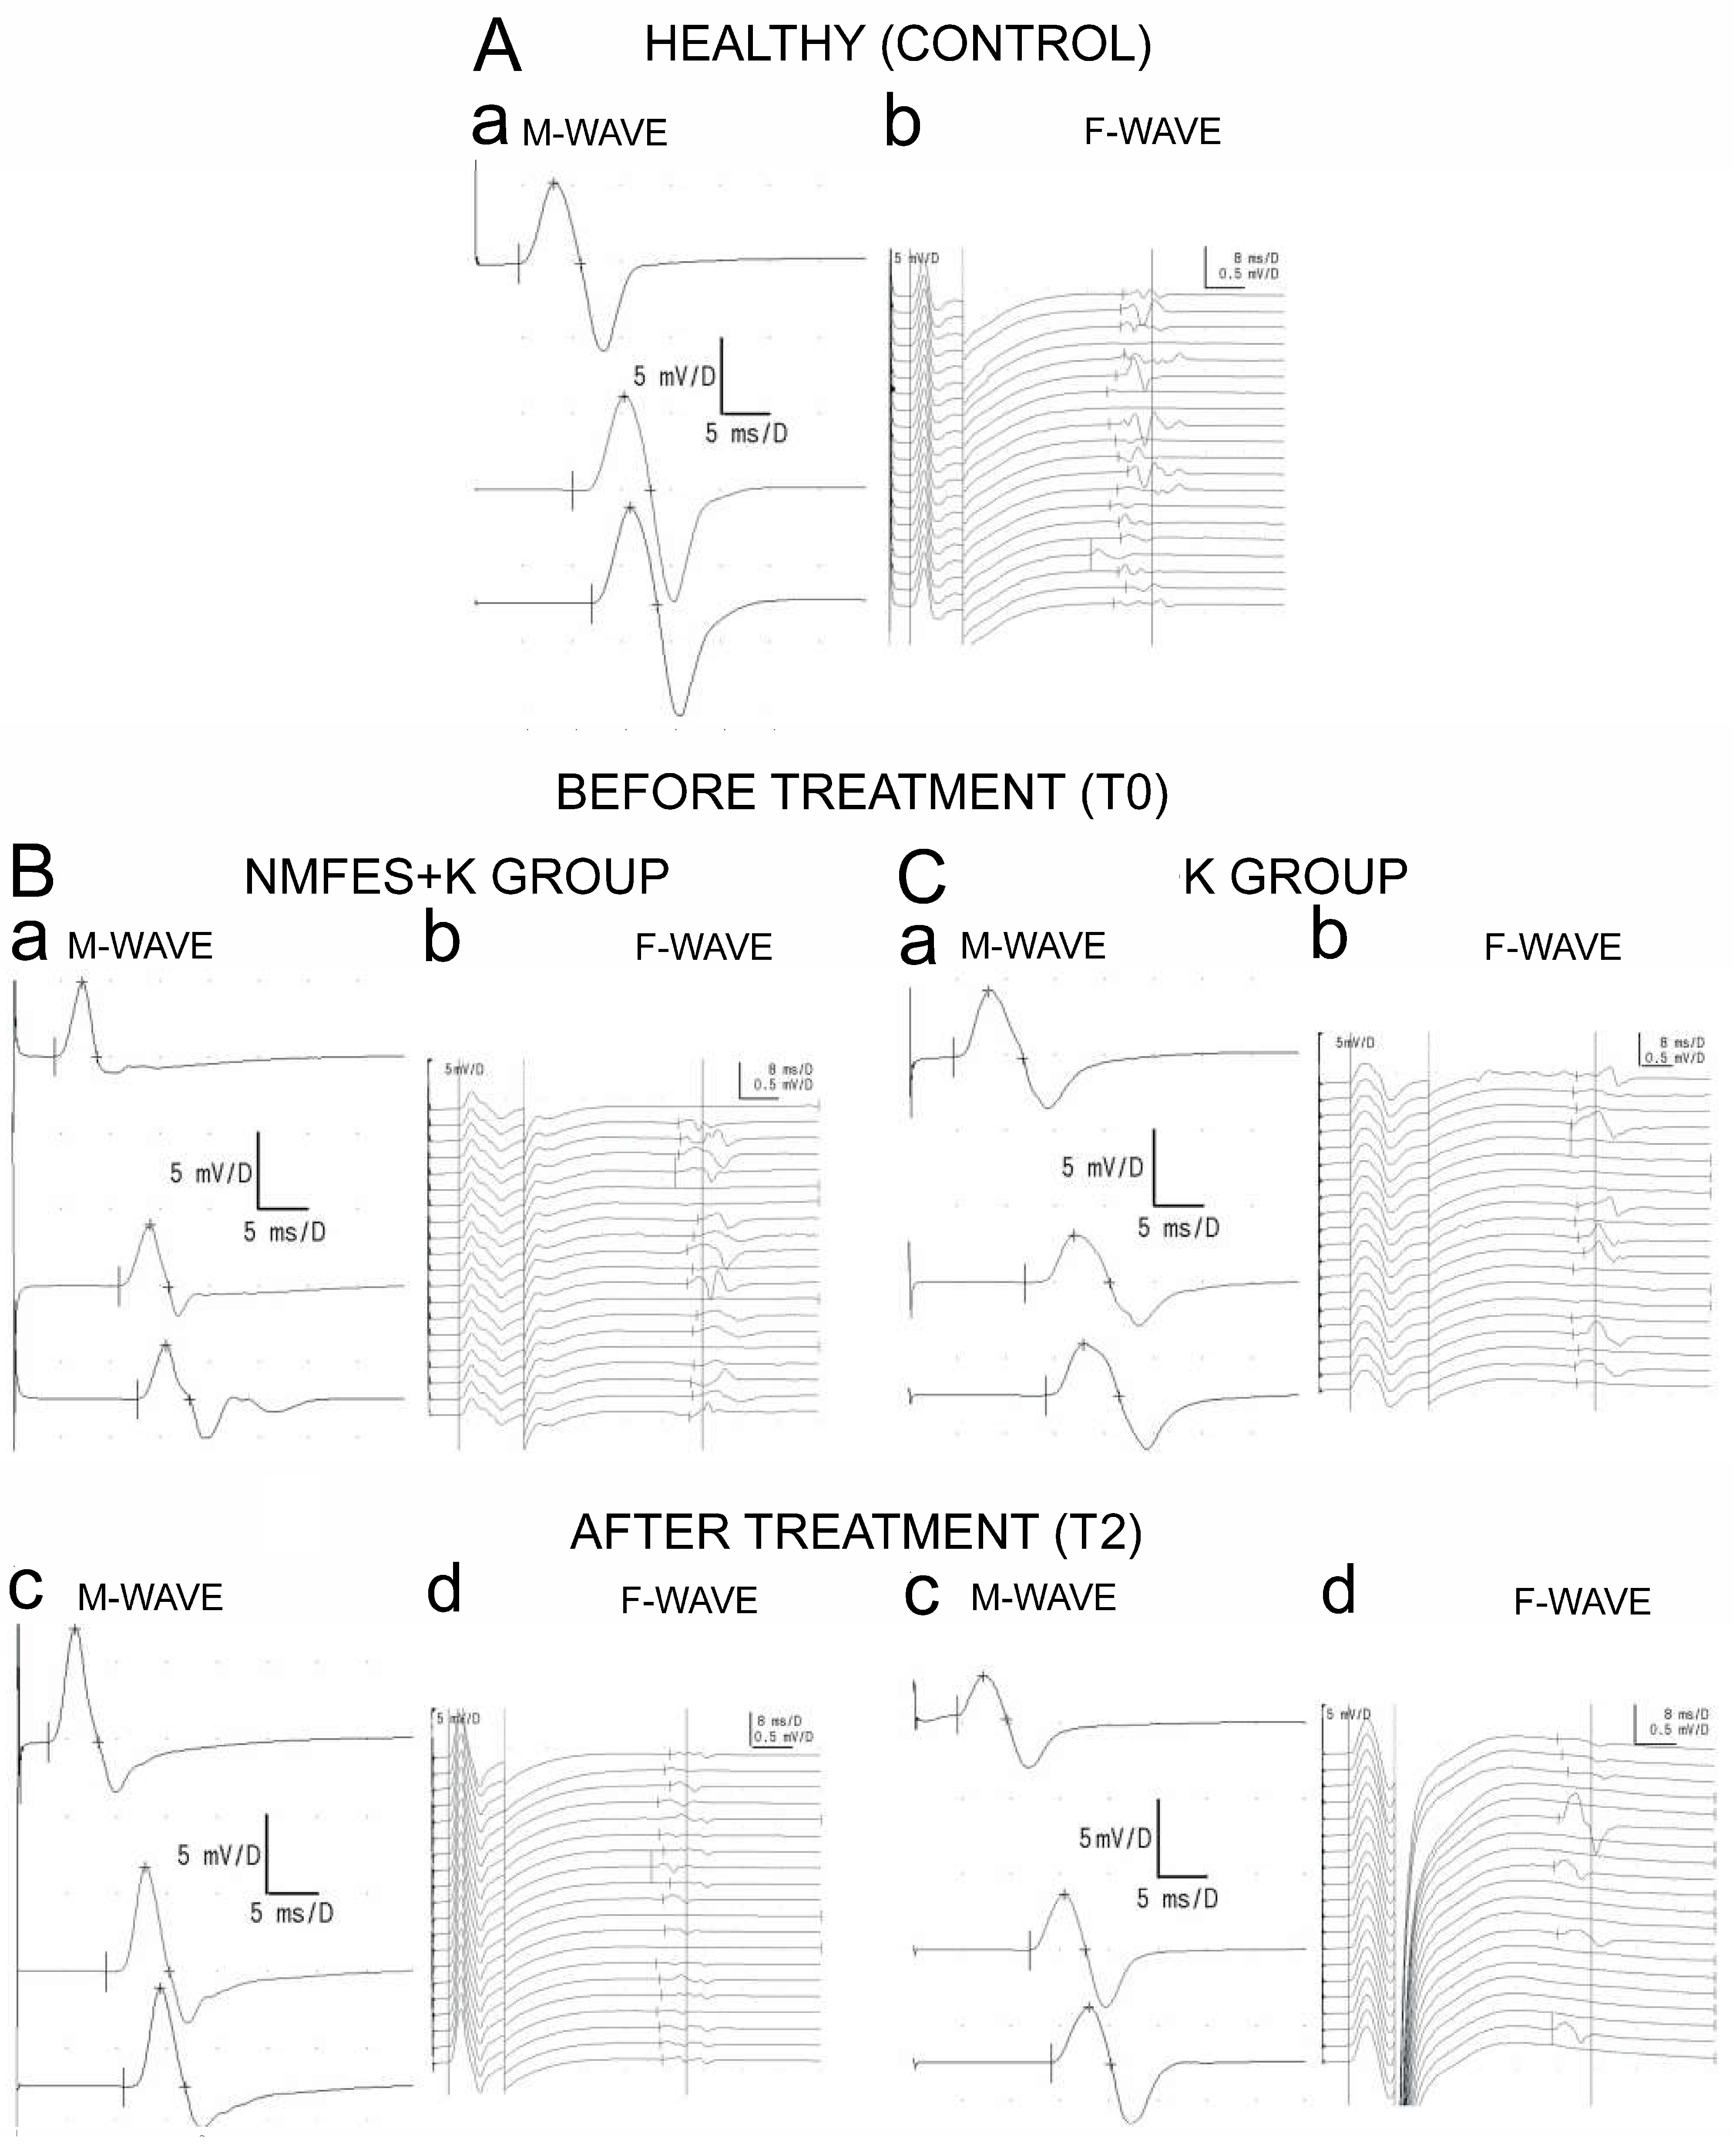

2.2. Neurophysiological Evaluation

3. Results